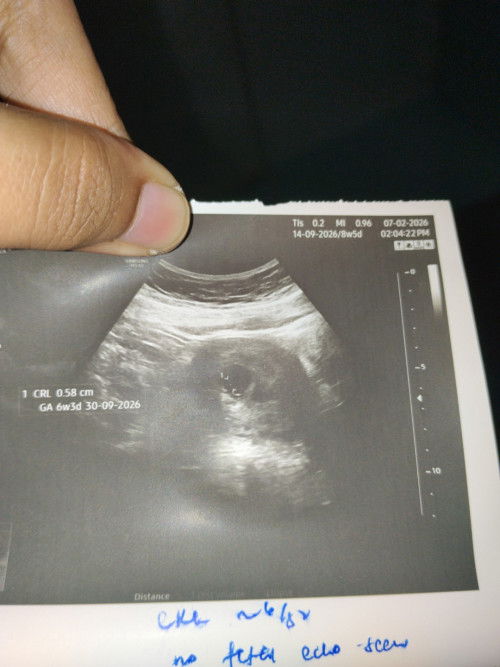

Kiraan usia kandungan

Kalau ikut my last period date .. usia kandungan should be around 8-9weeks. Tp tadi scan kandungan baru 6 weeks . Nnti kena repeat scan . What do you think mommies? Saya dah fikir yg tidak2 ni . Takut.

Normal kalau 1@2 minggu. Sy pun lewat seminggu masa 1st scan. Dr suruh dtg repeat scan Alhamdulillah dah ada jantung.